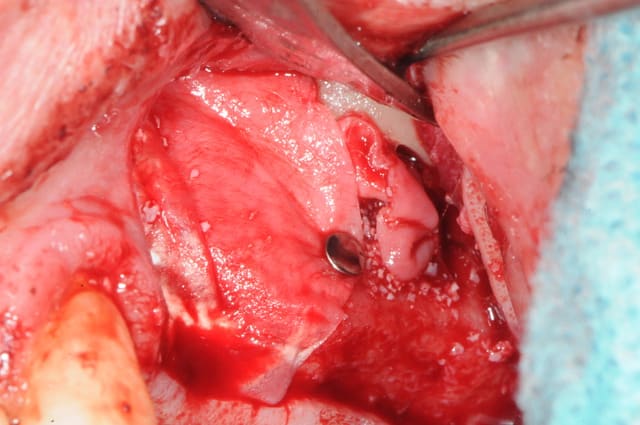

bref, la membrane s'est ouverte en cours d'intervention en faisant un petit "pok".

j'ai donc utilisé la technique de la double chaussette avec une membrane foulée dans le sinus.

ci joins photos...

exacte !

suivant l'importance de la perforation, les choses sont très différentes.

ici la perforation est trop grosse pour un simple pansement au collagène (qui se résorbe trop rapidement d'ailleurs).

il faut donc une vraie étanchéité donc, la poche de Loma.

ici, j'ai étendu le décollement sans abimer d'avantage la membrane et une fois suffisamment réclinée j'ai utilisé une membrane collagène.

mais il faut laisser les bords de la membrane en dehors de la fenêtre sinon, voilà ce qu'il se passera après quelques heures. même si vous en avez l'impression du contraire, l'activité respiratoire au sein du sinus suffit largement à décoller le lien entre les différentes membranes.